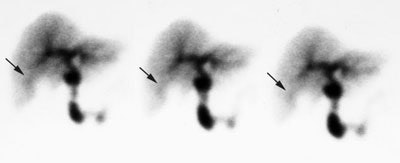

Acute Cholecystitis: The case below demonstrates the characteristic findings of acute cholecystitis. There is non-visualization of the gallbladder at one hour. There is a subtle rim of increased tracer activity about the gallbladder fossa ("rim sign"- see below). The gallbladder is markedly distended. There is mild hang-up of tracer in the left hepatic ductal system. Click the image to view the cine of this case (1 MB). Case courtsey of Dr. Jamie Montilla, MD |

Characteristic Scintigraphic Findings in Acute Cholecystitis:

Rim Sign:

Refers to increased pericholecystic hepatic activity without GB visualization- the rim sign is caused by severe inflammation extending into the adjacent liver, resulting in increased blood flow to that area, and increased delivery of radiotracer [20]. The rim sign appears as curvilinear band of increased activity along the hepatic margin above the GB fossa and is usually identified early in the examination (See image below). It may be due to increased flow and/or impaired hepatocyte radionuclide excretion. The rim sign is identified in about 25-35% of patients with acute cholecystitis [20], but it can also be seen in some patients with chronic cholecystitis. The positive predictive value for acute cholecystitis is about 95% when a rim sign is identified in association with non-visualization of the gallbladder at one hour [9]. Approximately 40% of patients who demonstrate the rim sign will have complicated cholecystitis (extensive necrosis, perforated or gangrenous GB), thus the presence of this sign indicates the need for more emergent surgery. Very rarely there may be gallbladder visualization in association with a rim sign- this should still be considered highly suspicious for acute or subacute cholecystitis. [6]

Rim sign in acute cholecystitis